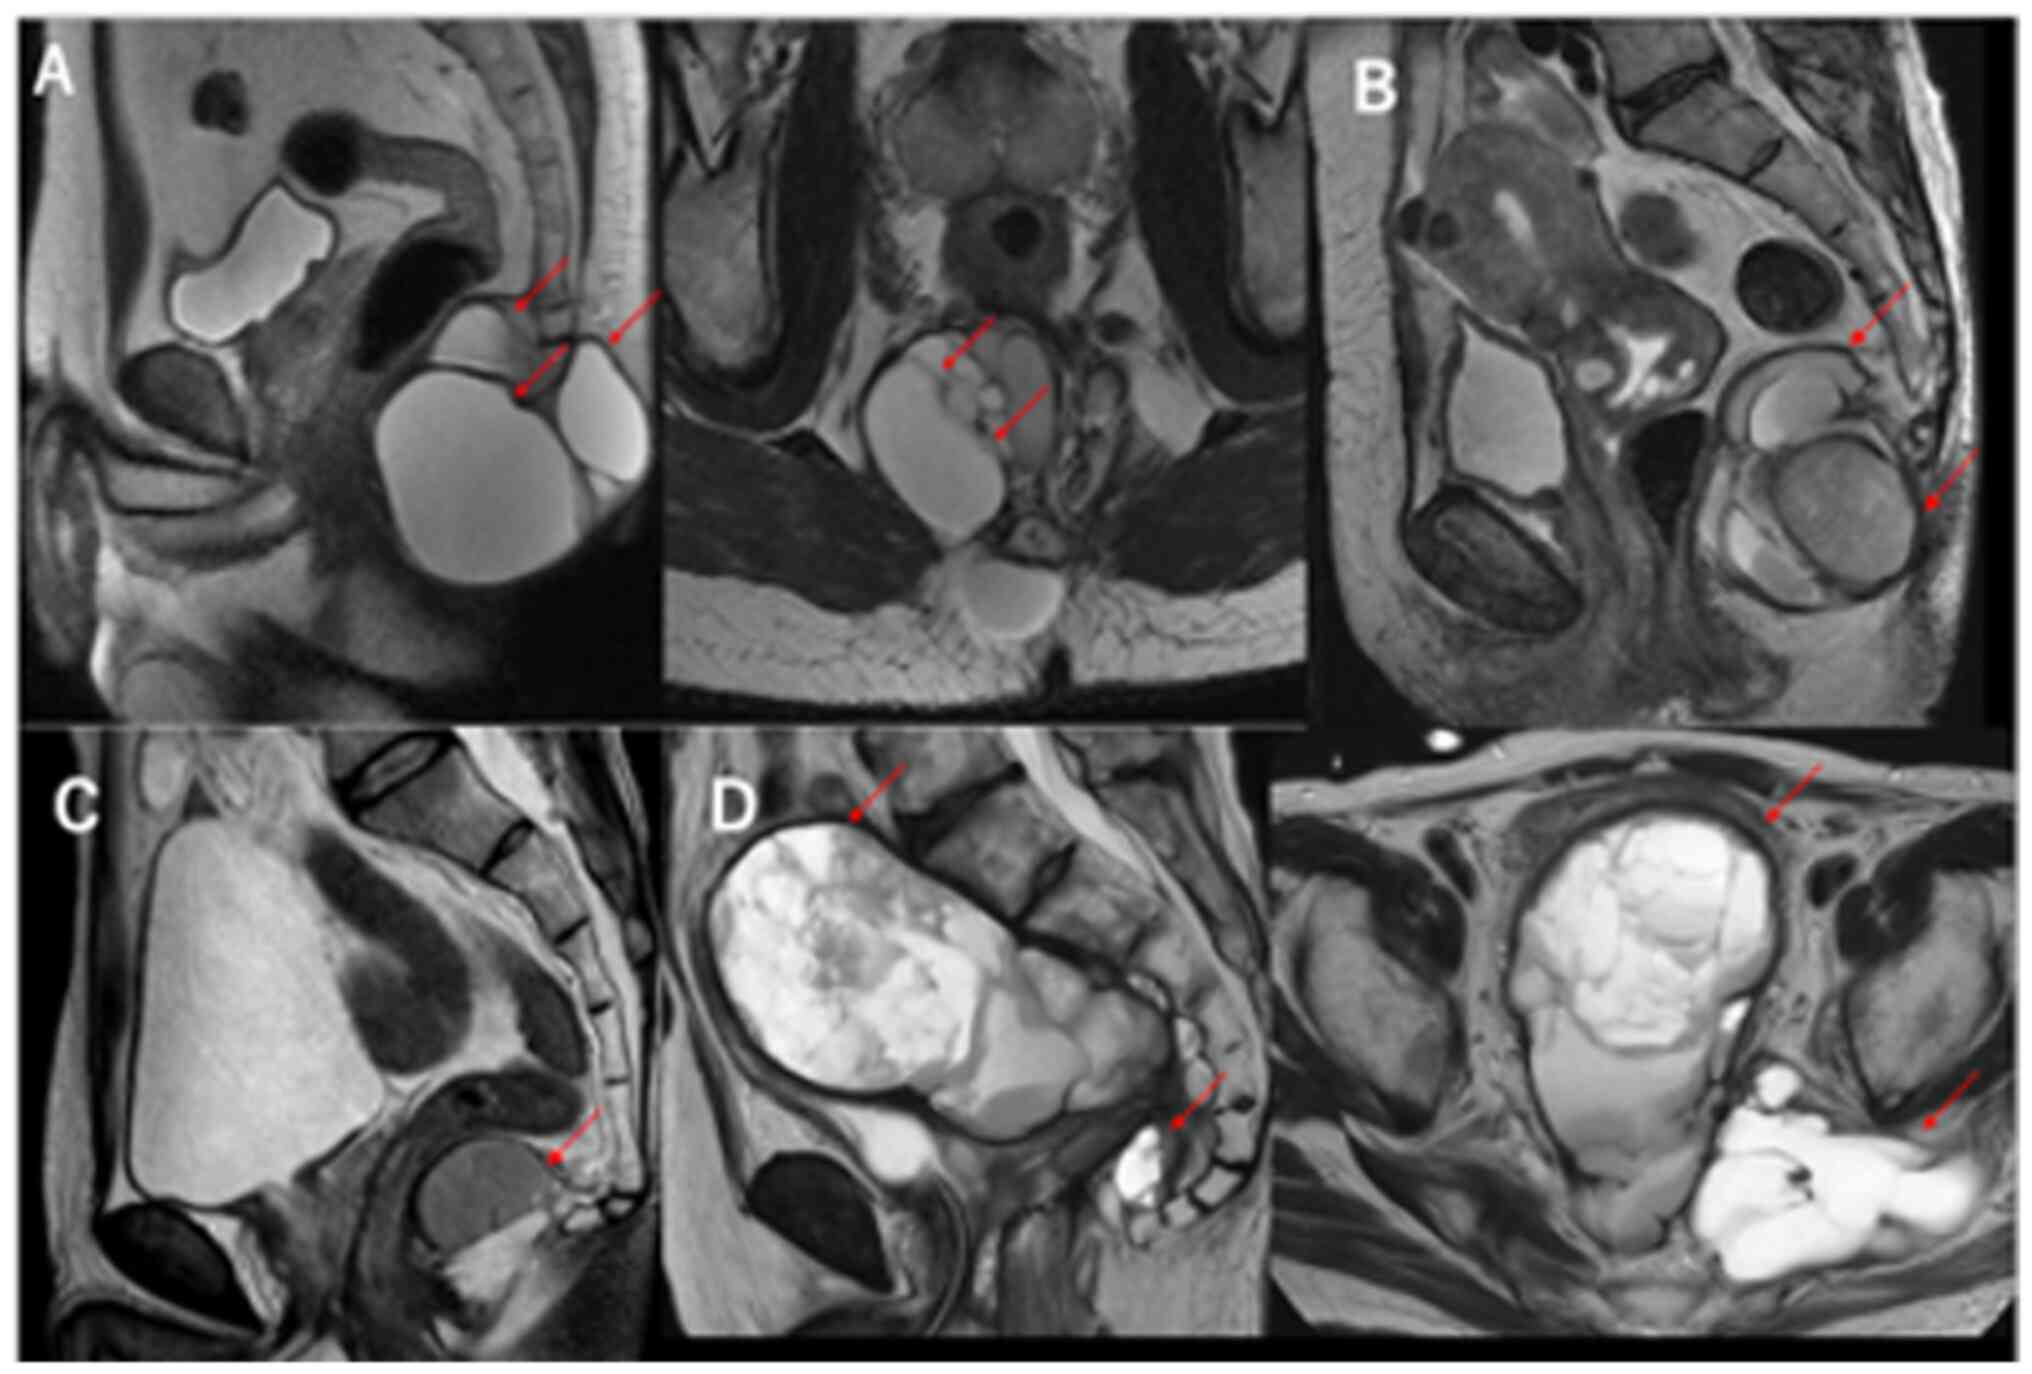

Magnetic resonance imaging (MRI) showed that all lesions were hypointense on T1-weighted imaging (T1WI) and hyperintense on T2WI. MRI T2WI sagittal images of cases 1–4 are presented in Fig. 1A-D, respectively. The cystic lesion in case 4 was enlarged laterally on the left in the MRI-axial image. A solid mass was present along with a large cystic lesion accompanying numerous septa in Patient 4 (Fig. 1D).

Figure 1.

Magnetic resonance imaging of tailgut cysts. (A) Well-circumscribed multilocular lesion, hyperintense on T2W1, in the retrorectal space (Patient 1, arrows). (B) Cystic lesion accompanied by daughter cyst, hyperintense on T2WI (Patient 2, arrows). (C) Focal cystic lesion, hyperintense on T2WI (Patient 3, arrow). (D) Large cyst with numerous small septa with a mass with a solid component, hyperintense on T2WI, in the presacral space (Patient 4, arrows). T2WI, T2-weighted imaging.